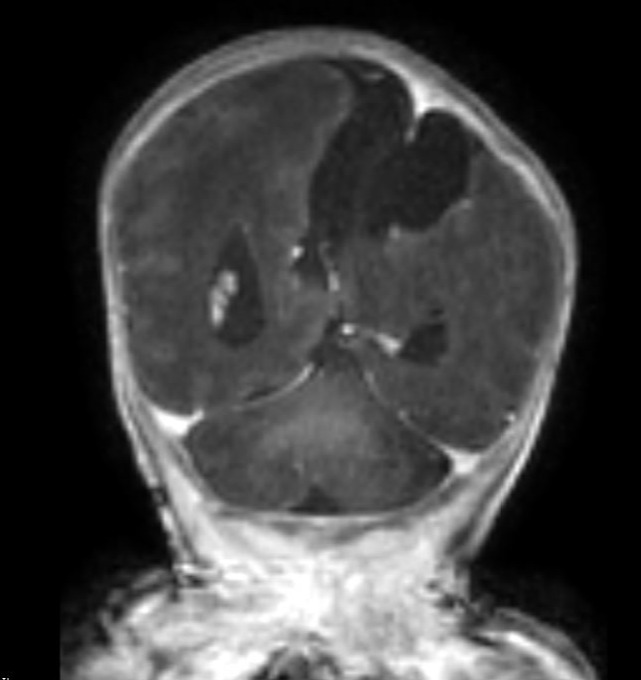

A 24-year-old gravida 1 with a dichorionic-diamniotic twin pregnancy at 16w1d gestation was evaluated by Maternal-Fetal Medicine who identified multiple possible cranio-facial abnormalities in Twin A on transabdominal ultrasound. This raised the concern for a possible chromosomal abnormality as well as holoprosencephaly as the cavum septum pellucidum was not visualized. A detailed transabdominal ultrasound performed at 16w1d provided the initial assessment of the abnormal-appearing left cerebrum of Twin A (Figure 1). The left cerebral ventricle was overall poorly visualized, however, the posterior aspect of the left ventricle appeared to be significantly more dilated compared to the normal-appearing right ventricle. The cavum septum pellucidum could not be visualized, the thalami appeared fused, and the temporal areas of the facies appeared more angulated than expected. The patient was scheduled for a fetal MRI which was performed at 19w1d gestation and showed complete architectural distortion involving the left cerebral hemisphere of Twin A, with a mass-like structure measuring approximately 2.4 x 2.3 x 1.8 cm, along with a loss of normal gray-white differentiation (Figure 2). The diagnoses based on this MRI were either a neoplastic growth or a migrational anomaly.

At 23w0d a limited fetal MRI was repeated (Figure 4). This study demonstrated, again, the supratentorial left hemispheric mass measuring 3.3 x 3.5 x 2.4 cm within the cerebrum of Twin A. Most notably, there was an interval increase in the size of the mass relative to the skull diameter, as well as a prominent mass effect on the contralateral hemisphere with an associated midline shift. This second fetal MRI finding was interpreted as most consistent with an enlarging intracranial neoplasm with the differential diagnoses including astrocytoma, intracranial teratoma, and glioblastoma multiforme; however, no distinctive features were noted to confirm one of these diagnoses. The interval growth of the mass was interpreted as characteristic of an aggressive fetal neoplasm; therefore, a migrational anomaly was seen as less likely.